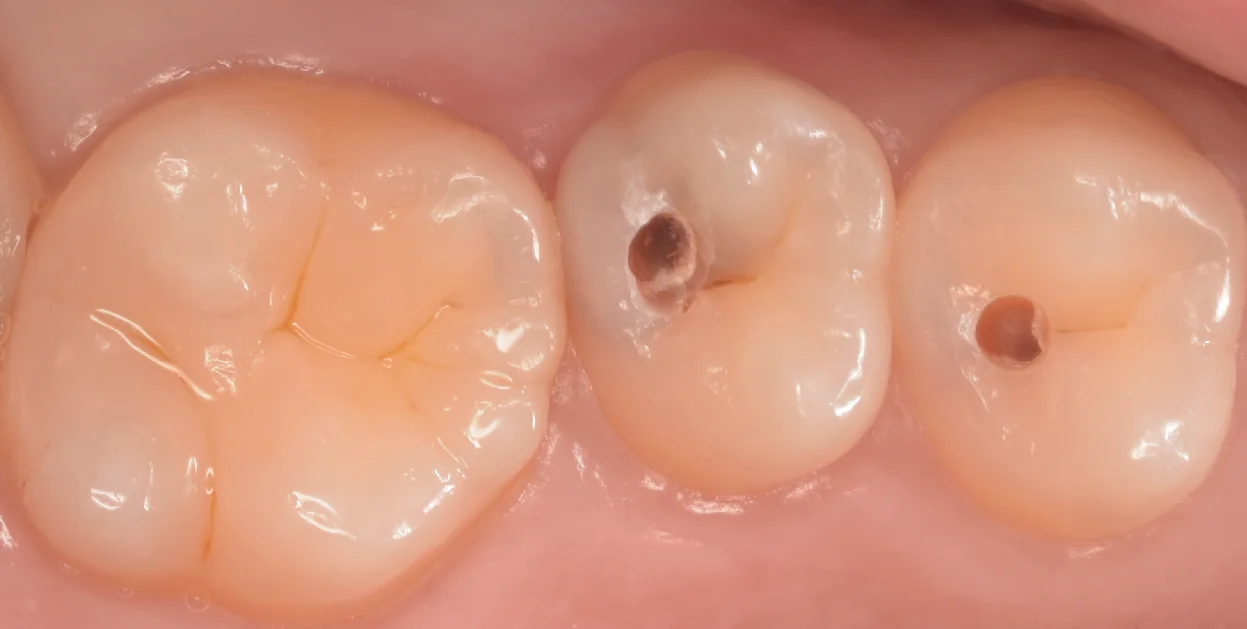

軽く削ってみたのがこちらの写真です。

虫歯を露出させると非常にわかりやすいと思います。

こんな感じで、歯の周辺で色が変わっている部分は内部で大きく広がっている部分になります。